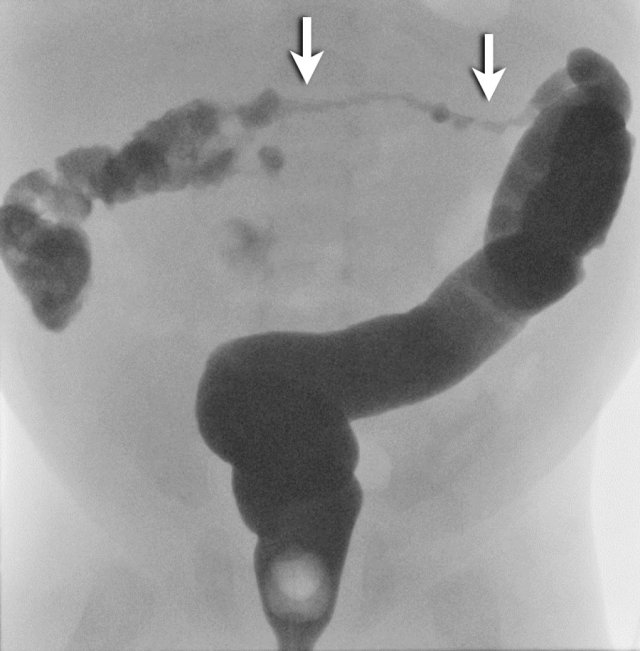

The findings are:

- Multiple dilated small bowel loops indicate a low obstruction

- Contrast enema show a small caliber of the rectum compared to the caliber of the sigmoid

- The rectum shows saw tooth contractions.

Diagnosis:

Short segment Hirschsprung disease.